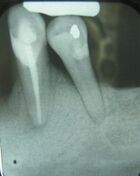

There are many types of investigations in diagnosis of oral and maxillofacial diseases, including screening tests, imaging (radiographs, CBCT, CT, MRI, ultrasound) and histopathology (biopsy).[5]

A biopsy is indicated when the patient's clinical presentation, past history or imaging studies do not allow a definitive diagnosis. A biopsy is a surgical procedure that involves the removal of a piece of tissue sample from the living organism for the purpose of microscopic examination. In most cases, biopsies are carried out under local anaesthesia. Some biopsies are carried out endoscopically, others under image guidance, for instance ultrasound, computed tomography (CT) or magnetic resonance imaging (MRI) in the radiology suite. Examples of the most common tissues examined by means of a biopsy include oral and sinus mucosa, bone, soft tissue, skin and lymph nodes.[6]